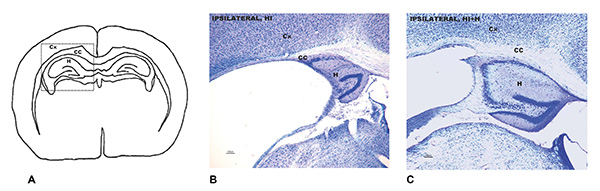

A: zona del cerebro afectada por la lesión cerebral por hipoxia e isquemia. B: Análisis neuropatológico que muestra el daño cerebral en ratones adultos que siendo bebés sufrieron la lesión y no recibieron estimulación sensorial. C: Análisis neuropatológica de la misma zona en los ratones adultos que sí la recibieron.

A: zona del cerebro afectada por la lesión cerebral por hipoxia e isquemia. B: Análisis neuropatológico que muestra el daño cerebral en ratones adultos que siendo bebés sufrieron la lesión y no recibieron estimulación sensorial. C: Análisis neuropatológica de la misma zona en los ratones adultos que sí la recibieron.